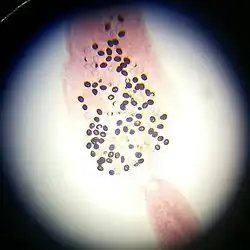

К группе биогельметинов относятся плоские и круглые черви, такие как трематод, цестод, нематод[2].

Типичные биогельминты делятся на три группы[3]:

- паразиты, которые развиваются в организме живых существ, полностью вне окружающей среды (такова большая часть биогельминтов);

- те, кто нуждаются во внешней среде лишь для заражения промежуточных хозяев (также большая группа);

- нуждающиеся во внешней среде для развития на ранних стадиях; затем личинка продолжает развитие в промежуточном хозяине. В отличие от геогельминтов, личинки которых являются заразными для человека, ранняя стадия развития биогельминтов во внешней среде не представляет для человека никакой опасности. Чтобы личинка была жизнеспособна, она должна развиваться в теле промежуточного хозяина.